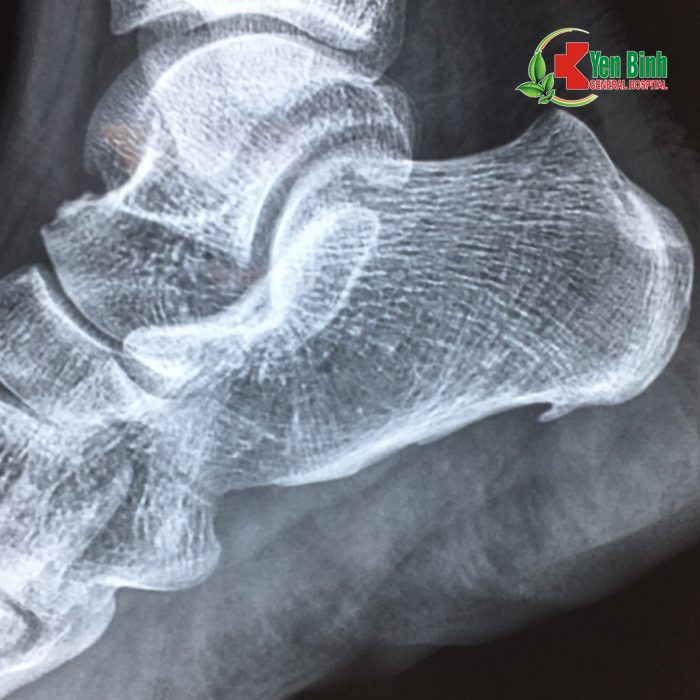

???Bà Lương Thị T(50 tuổi), bị đau gót chân phải gây khó khăn trong sinh hoạt và đi lại, đã đến bệnh viện Đa khoa Yên Bình Thái Nguyên thăm khám. Các bác sỹ tiến hành chụp Xquang, thăm khám và chẩn đoán bà T bị viêm cân gan chân phải có gai xương gót. Người bệnh được chỉ định phẫu thuật nội soi cắt cân gan chân và mài bỏ gai xương gót.

Hình ảnh chụp Xquang của người bệnh Lương T.T thấy rõ gai xương gót